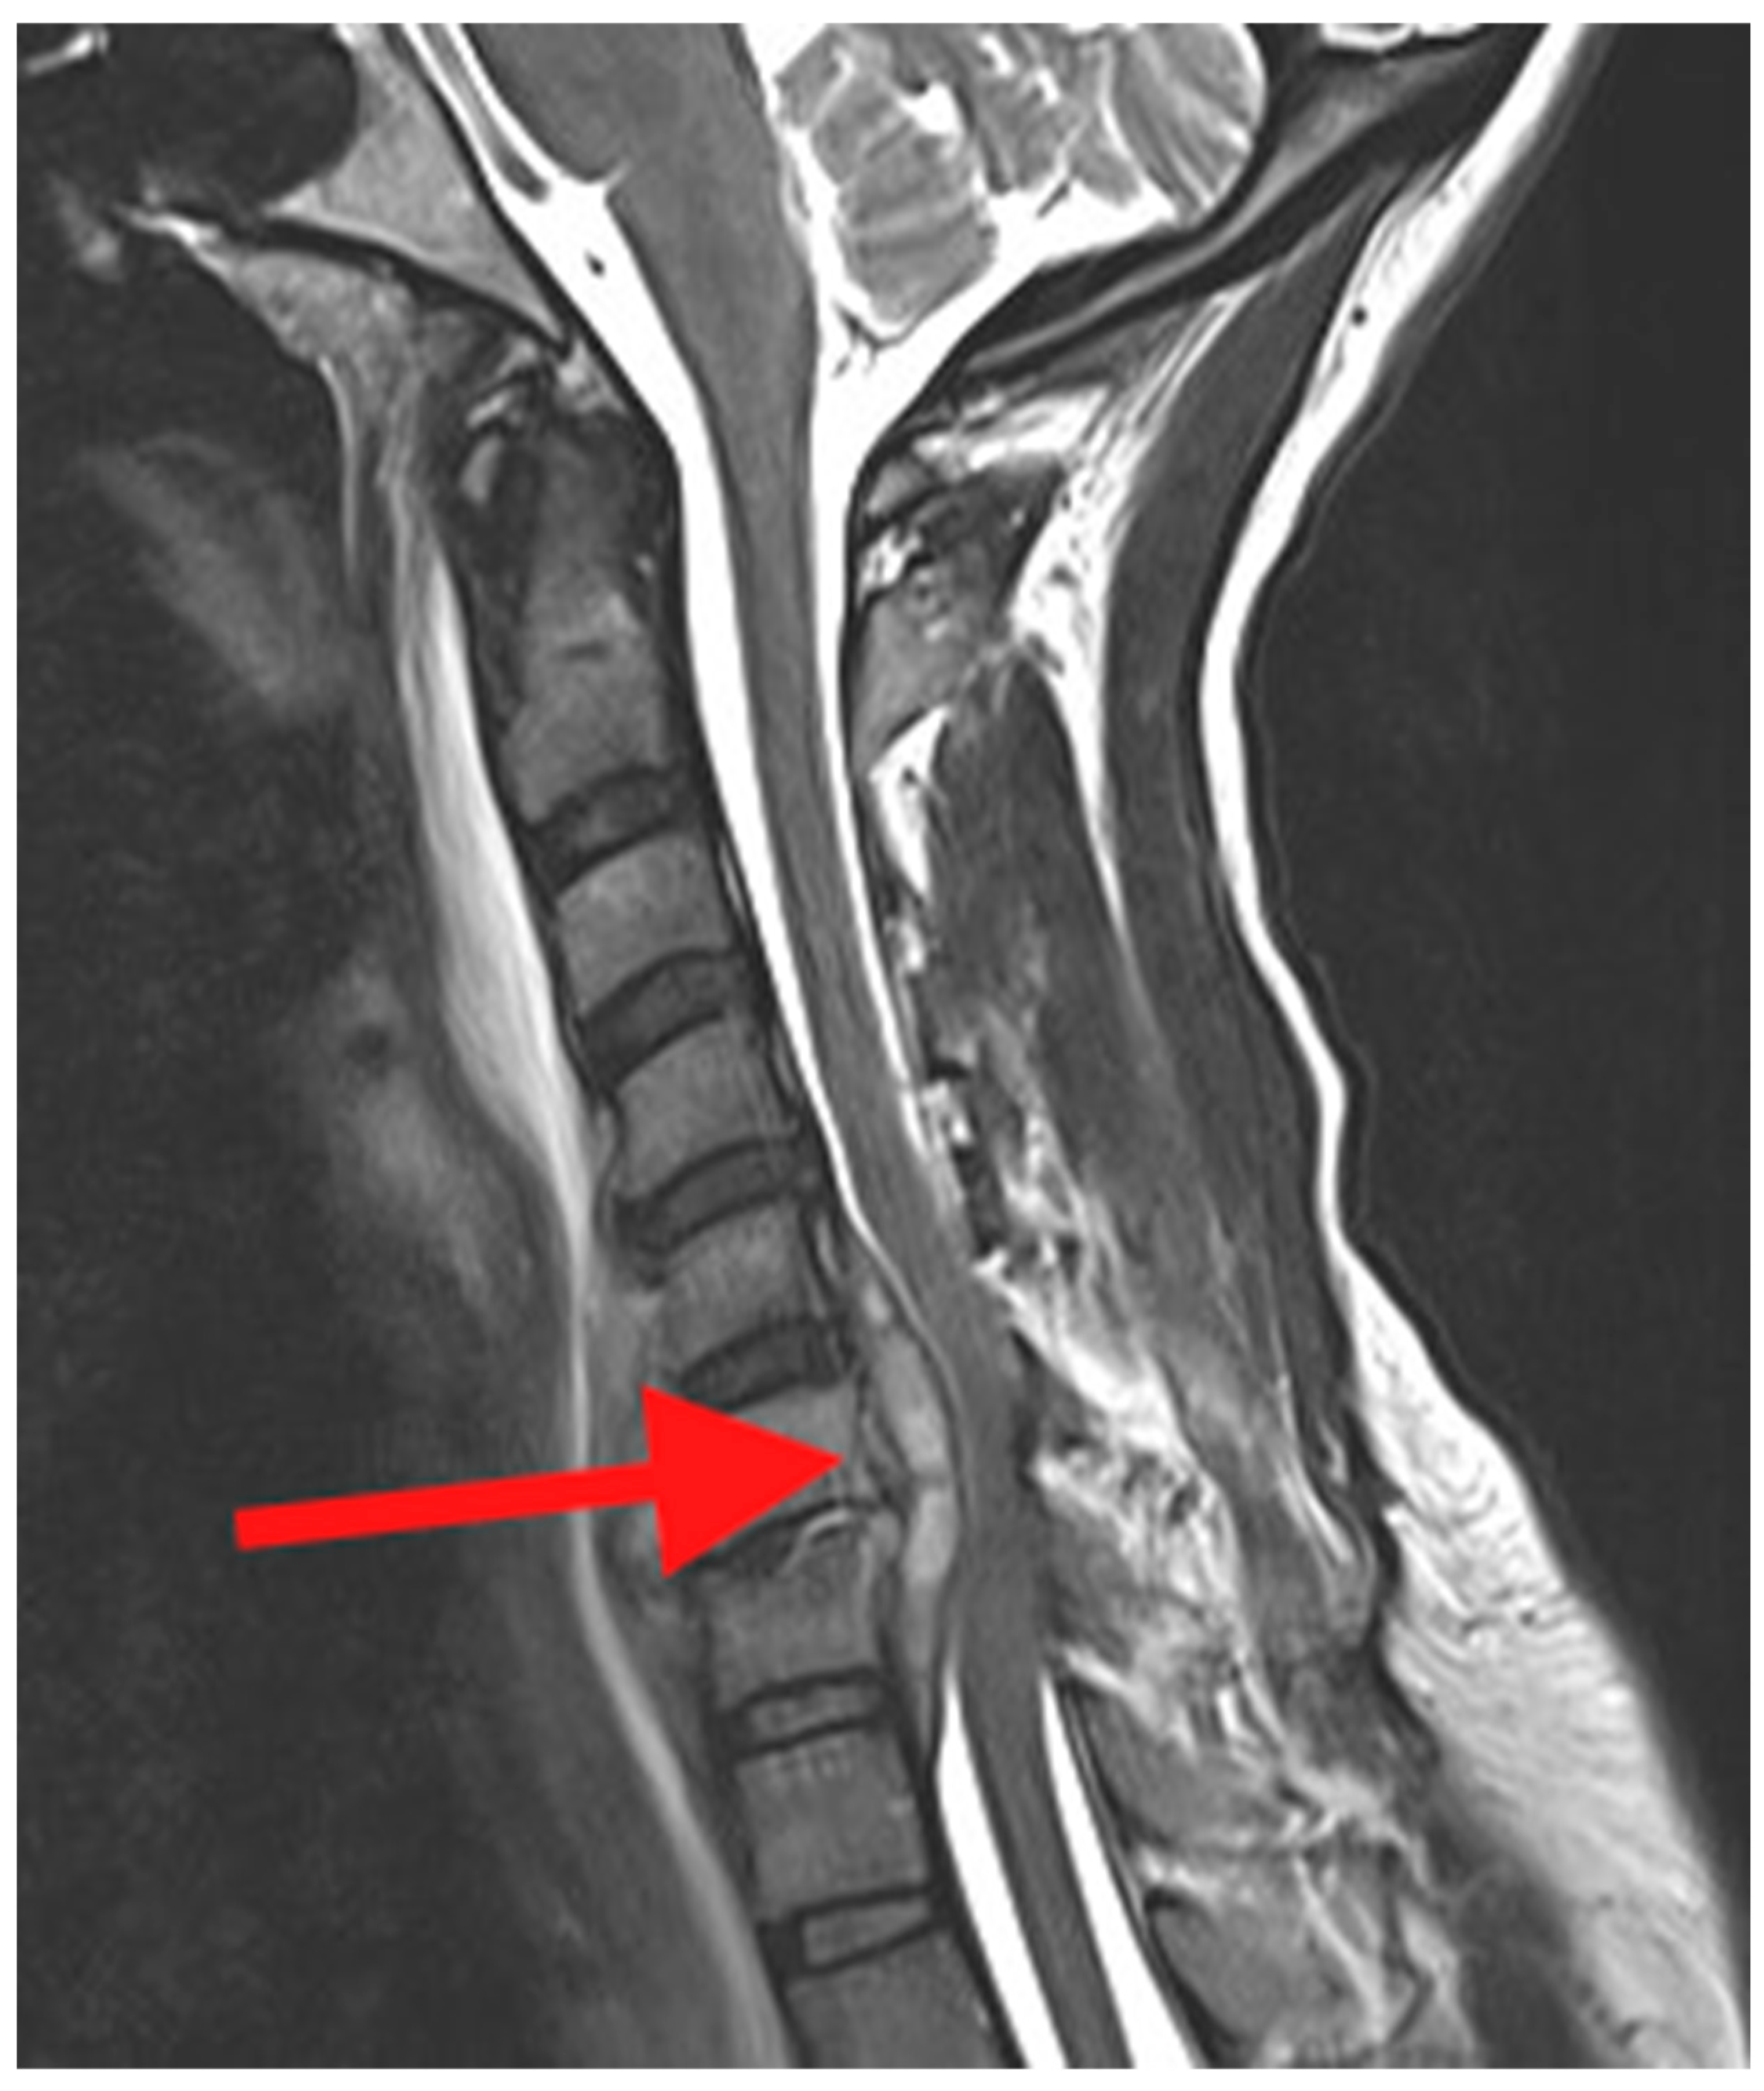

Magnetic resonance imaging (MRI) is the imaging modality of choice in the evaluation of PSD. Compared with CT, MRI would demonstrate a better visualization of the soft tissues including any associated abscesses, muscles and ligaments, spinal cord, cauda equina, and nerve roots (Figure 3). MRI will also provide earlier detection of the infection compared with plain radiographs and CT. It is recommended if PSD is identified in one region of the spine, and that the other regions be imaged to identify “skip” lesions [18].

Figure 3. Sagittal T2 weighted MRI of the cervical spine. The red arrow points to an epidural abscess behind the C5, 6, and 7 vertebral bodies and compression of the ventral spinal cord.